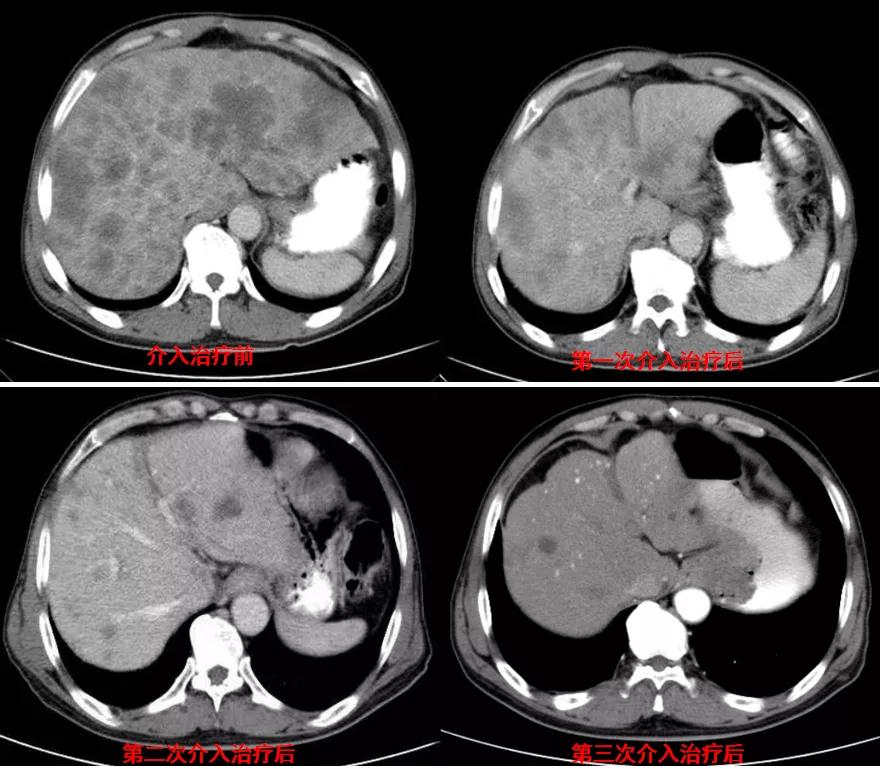

诊治经过:2021年5月16日患者行第三次经皮动脉化疗灌注栓塞术(铂类+氟尿嘧啶)治疗,并继续联合吡咯替尼治疗。结果见图4。

图4

总结:本例患者为胃癌IV期,伴肝转移及淋巴结转移,经介入联合吡咯替尼治疗后,肝转移灶显著缩小。治疗前肿瘤标志为:癌胚抗原3574.3ng/ml、CA12-5 650U/ml、CA19-9 1212U/ml、CA15-3 333U/ml;治疗后肿瘤标志为:癌胚抗原7.6ng/ml、CA12-5 12.8U/ml、CA19-9 17.4U/ml、CA15-3 6.7U/ml。治疗后,肿瘤标志物显著降低,且腹部CT结果显示该患者肝转移病灶较治疗前明显减少。患者目前带瘤总生存达10个月,病情稳定。